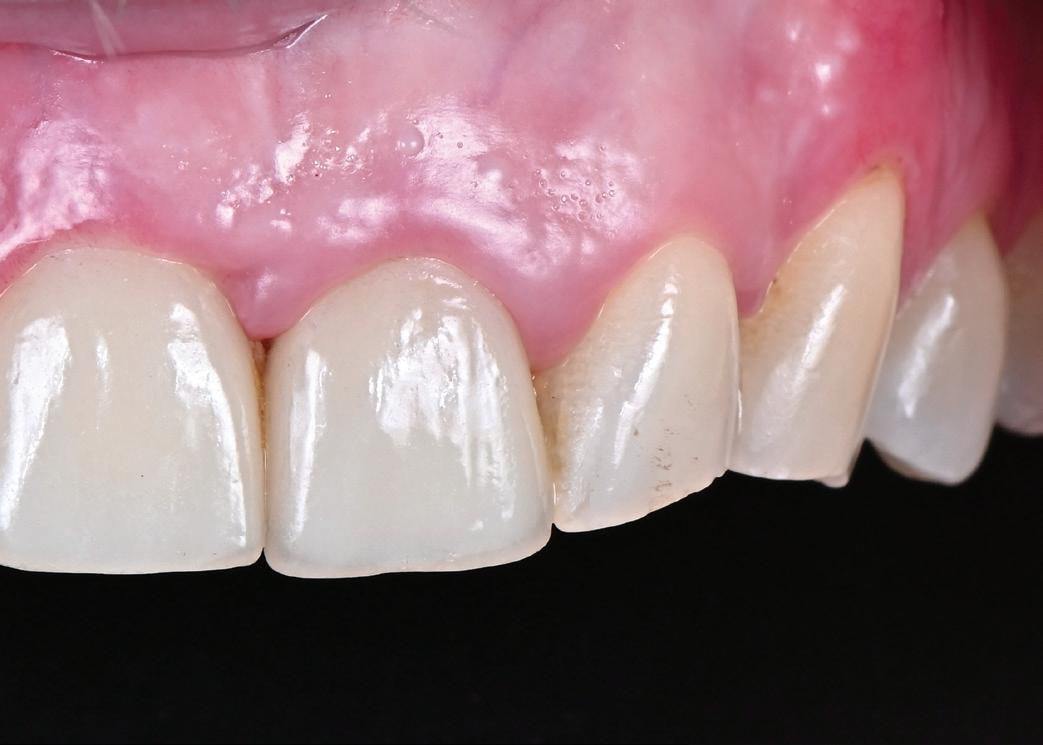

SITE AUGMENTATION Reconstituirea țesutului moale periimplantar și papilar în zona estetică

RECONSTITUIREA țesuturilor moi periimplantare. Scopul acestui raport de caz este de a demonstra procedurile chirurgicale utilizate pentru corectarea unui defect al țesuturilor moi periimplantare folosind țesutul moale interdentar în combinație cu tuberozitatea ca locație donatoare de țesut conjunctiv, utilizând o abordare prin tunelizare într-o zonă estetică.

și „punte cu trei unități”, în prezent fiind la egalitate cu majoritatea sistemelor de titan. Deși datele pe termen lung nu au confirmat încă aceste rezultate bune, succesul de până acum este încurajator, astfel încât clinicienii profită de beneficiile clinice ale dioxidului de zirconiu în practica zilnică, introducând implanturile ceramice ca opțiune suplimentară în spectrul de opțiuni alături de cele de titan (fig. 1). Chiar

Totuși, ca și în cazul implanturilor de titan, în rare cazuri, și la cele ceramice poate apărea o recesie nedorită cu expunerea umărului implantar. Cu toate acestea, din punct de vedere estetic, această recesie a gingiei inflamate este posibil să fie mult mai bine tolerată de către pacienții preocupați de marginile întunecate ale implanturilor de titan (fig. 2).

În plus, aceste proprietăți bioinerte par să aibă și beneficii în ceea ce privește dezvoltarea periimplantitei și calitatea țesuturilor moi. În comparație cu titanul, dioxidul de zirconiu prezintă acumulare de placă și aderență bacteriană mai redusă, precum și o grosime mai mică a biofilmului depus. Și fluxul sanguin circulant către țesuturile moi este mai asemănător cu cel al unui dinte natural în cazul ceramicii față de titan, care oferă flux sanguin redus semnificativ. Se știe că o circulație sanguină mai bună înseamnă țesuturi moi mai sănătoase, care, la rândul lor, prezintă rezultate estetice îmbunătățite. Deși deocamdată lipsesc dovezile pe termen lung pentru implanturile ceramice, sunt disponibile rezultatele inițiale la 3 și 5 ani, iar tendința, susținută de studii preclinice și experiența clinică, este că dioxidul de zirconiu demonstrează același rezultat - iar în unele studii chiar o pierdere osoasă marginală mai redusă față de implanturile de titan. În această perioadă încă nu s-a descris clinic periimplantită.

Trebuie remarcat, totuși, că în cazul implanturilor ceramice, ca și în al celor de titan, cementita, adică inflamația periimplantară cauzată de reziduurile de ciment, poate duce la periimplantită. În plus, la implanturile din dioxid de zirconiu poate apărea supraîncălzirea la înșurubarea implantului în os, iar suprafețele excesiv de aspre sau poroase ale implantului pot cauza defecte osoase periimplantare din cauza termoconductivității reduse a materialului. Deși sunt necesare mai multe dovezi științifice care să demonstreze o tendință mai scăzută spre periimplantită în cazul implanturilor ceramice, argumentul esențial pentru aceste implanturi bazat pe experiența clinică este starea excelentă și aproape constant lipsită de inflamație a țesuturilor moi periimplantare (fig. 3).

1. Implanturi din titan (stânga) și zirconiu (dreapta). 2. Recesii la implanturile ceramice (stânga) și din titan (dreapta). 3. Țesut moale cu implant din zirconia, lipsit de inflamație.